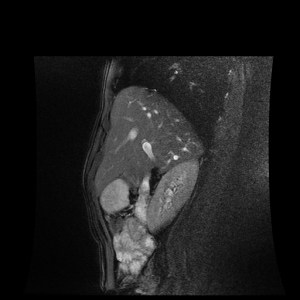

test_MR_NO_20180123_015